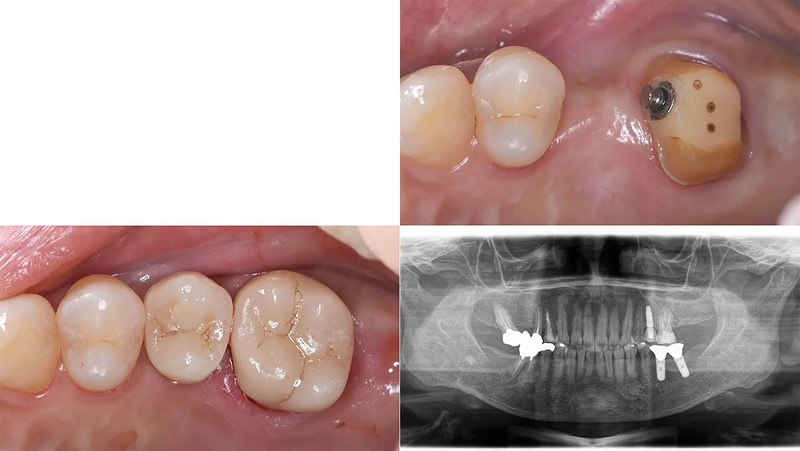

Case03部分矯正とインプラントで歯列を整えた症例

メインテナンスに通っていた患者さんであるとき、左上第2大臼歯のかぶせ物が脱離して来院されました。第2大臼歯は歯根破折をしており、残念ながら予後不良で抜歯と診断しました。元々、第2小臼歯が欠損しており、第1大臼歯がそのスペースに倒れこんでいる歯列不正がありました。この機会に歯列を整えて、インプラントをしましょうと提案しました。承諾していただき、5か月の部分矯正後、インプラントを埋入しました。3年経ちましたが経過は順調です。

初診 2016.1.21

左上7番 歯根破折 ⇒ 抜歯 左上6番 部分矯正開始 2016.2.8

左上6番 部分矯正終了 2016.7.12 ファイナル 2016.9.27

治療後3年 2019.10.12